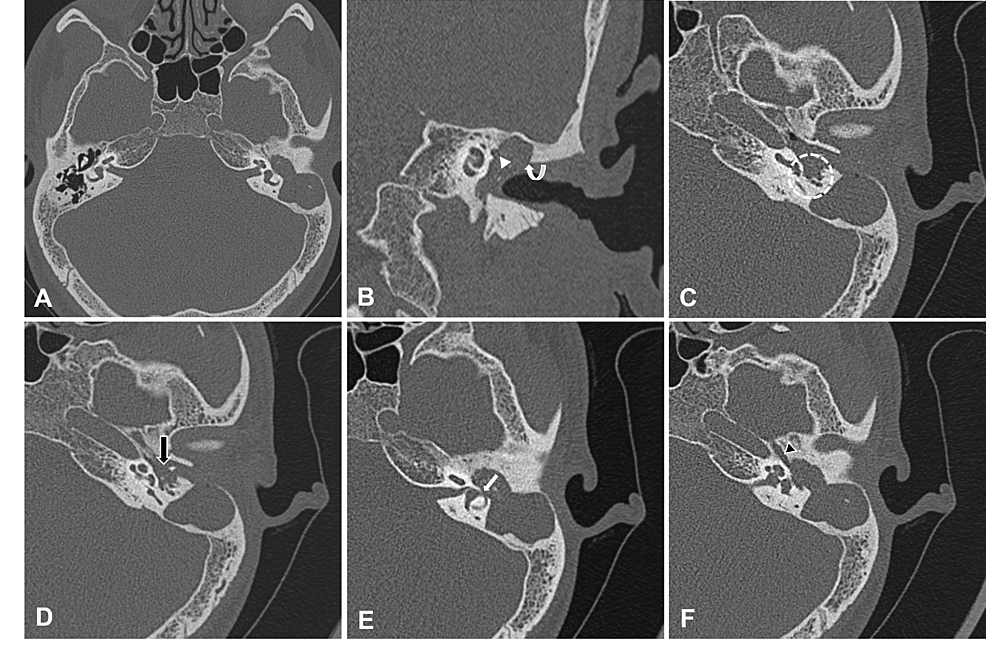

Axial (horizontal) CT of the right temporal bone showing cholesteatoma... Download Scientific What Is Cholesteatoma Of The Ear Cholesteatoma is an abnormal growth in your middle ear behind your eardrum. A cholesteatoma is a benign mass that consists of keratinizing squamous cell epithelium that grows in the middle ear. Cholesteatoma is an abnormal skin growth in the middle ear behind the eardrum. It can be congenital (present from birth), but typically. This serious ear condition can be present. What Is Cholesteatoma Of The Ear.

External Auditory Canal Cholesteatoma Clinical and Imaging Spectrum American Journal of What Is Cholesteatoma Of The Ear It often starts when a perforation (hole) in the eardrum allows. Cholesteatoma is an abnormal skin growth in the middle ear behind the eardrum. This serious ear condition can be present at birth or develop later in life, often as a result of multiple ear. Cholesteatoma is an accumulation of squamous epithelium and keratin debris that usually involves the middle. What Is Cholesteatoma Of The Ear.

Cureus Temporal Bone Cholesteatoma Typical Findings and Evaluation of Diagnostic Utility on What Is Cholesteatoma Of The Ear Cholesteatoma is an abnormal growth in your middle ear behind your eardrum. Cholesteatoma is an abnormal skin growth within the middle ear. Cholesteatoma is an accumulation of squamous epithelium and keratin debris that usually involves the middle ear and mastoid. A cholesteatoma is a benign mass that consists of keratinizing squamous cell epithelium that grows in the middle ear. It. What Is Cholesteatoma Of The Ear.